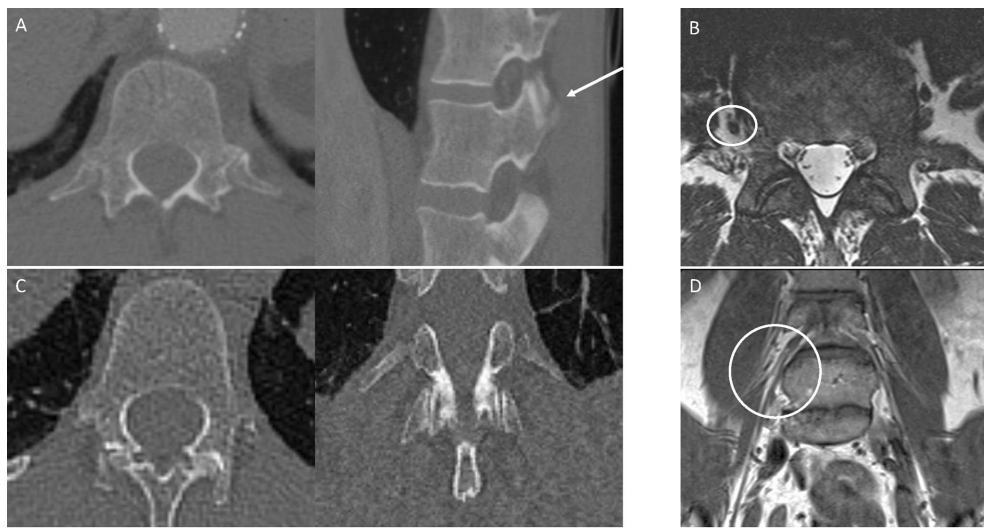

为解决胸腰段移行椎(TLTV)导致的脊柱标记不一致问题,研究人员开展椎体形态学分类(VSBC)研究。通过对比连续计数法(CCBC)、肋骨分类法(RBC/RLBC)和形态学法,发现VSBC在1242例CT数据中实现100%神经形态符合率及更高可靠性,为脊柱手术精准定位提供新标准。